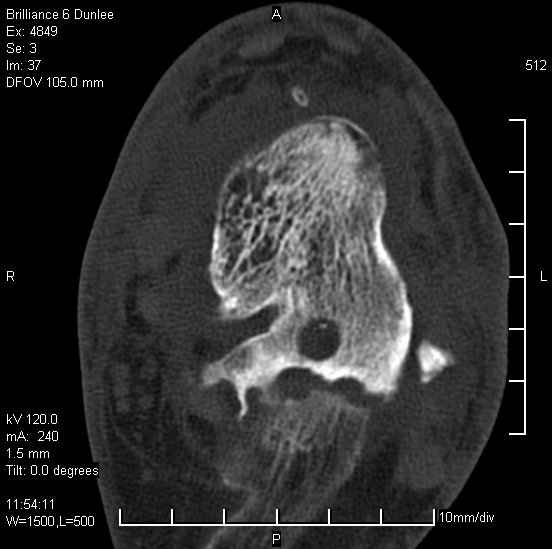

На лечении находится пациент 35 лет. Травма в сентябре 2008 г.- открытый вывих таранной кости

В день травмы ПХО, вправление вывиха, трансартикулярная фиксация. Рана зажила первично. С января нагрузка на конечность. С конца апреля- болевой синдром. На рентгенограммах и КТ признаки ас. некроза таранной кости, артроз подтаранного и голеностопного суставов.